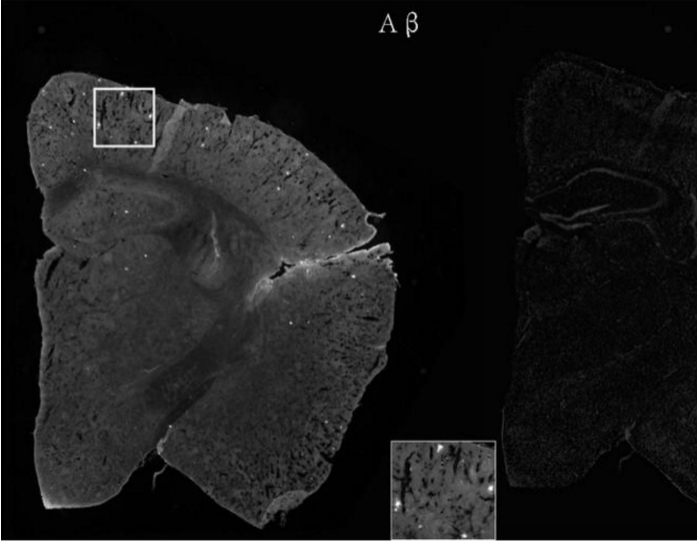

选取若干只4个月大的APP/PS1小鼠并随机分为两组,即实验组和对照组,分别用乳双歧杆菌Probio-M8和生理盐水喂养45天,收集小鼠粪便样本和脑内淀粉样β(Aβ)斑块样本,并进行分析。

实验结果参见图 1和图 2。两组数据对比分析得出,持续灌胃 45天乳双歧杆菌 Probio?M8的小鼠脑中Aβ斑块数量相比灌胃生理盐水组(对照组)有显著减少,其中面积较大的Aβ斑块数量也有所下降。证明了通过口服乳双歧杆菌Probio?M8干预4月龄APP/PS1小鼠可减少阿尔兹海默症特殊病理特征?Aβ斑块数量及面积。

[0015]图1为灌胃生理盐水组的小鼠大脑切片Aβ染色图